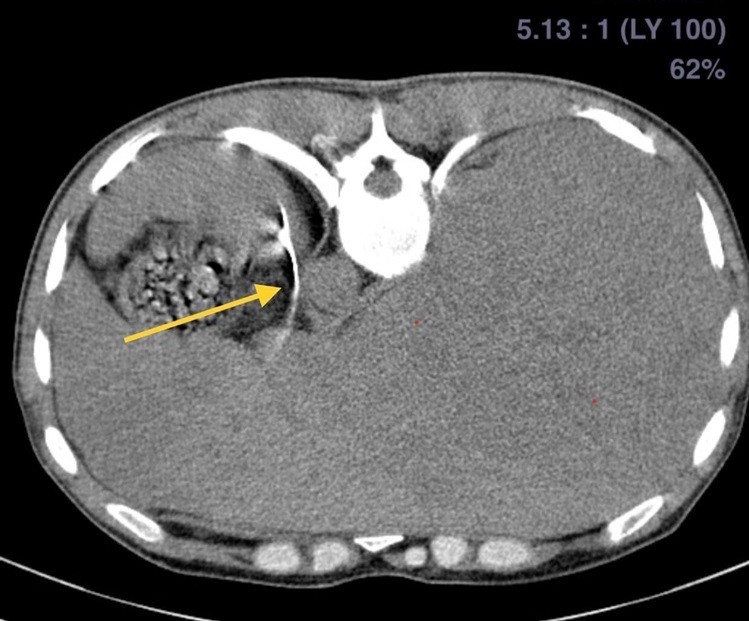

Ung thư gan đã gây tổn thương lan rộng trong cơ thể người bệnh, gây đau nhiều. Bác sĩ Trịnh Tú Tâm, Trưởng đơn vị Điện quang Can thiệp và Điều trị đau, Bệnh viện Hữu Nghị, ngày 3/11 thực hiện kỹ thuật diệt hạch đám rối thân tạng bằng cồn tuyệt đối để giảm đau cho bệnh nhân.

Kỹ thuật diệt hạch bằng cồn tuyệt đối, bệnh nhân không cần gây mê, không mất máu. Dưới hướng dẫn của máy cắt lớp vi tính, bác sĩ đưa chiếc kim nhỏ vào tới vị trí hạch đám rối thân tạng, sau đó tiêm cồn tuyệt đối để diệt hạch. Thực hiện kỹ thuật cần có hướng dẫn của các phương tiện chẩn đoán hình ảnh như siêu âm, cắt lớp vi tính, màn tăng sáng. Đường kim chọc vào đám rối thân tạng phải chính xác tuyệt đối, tránh làm tổn thương các tạng trong ổ bụng hoặc mạch máu khi can thiệp.